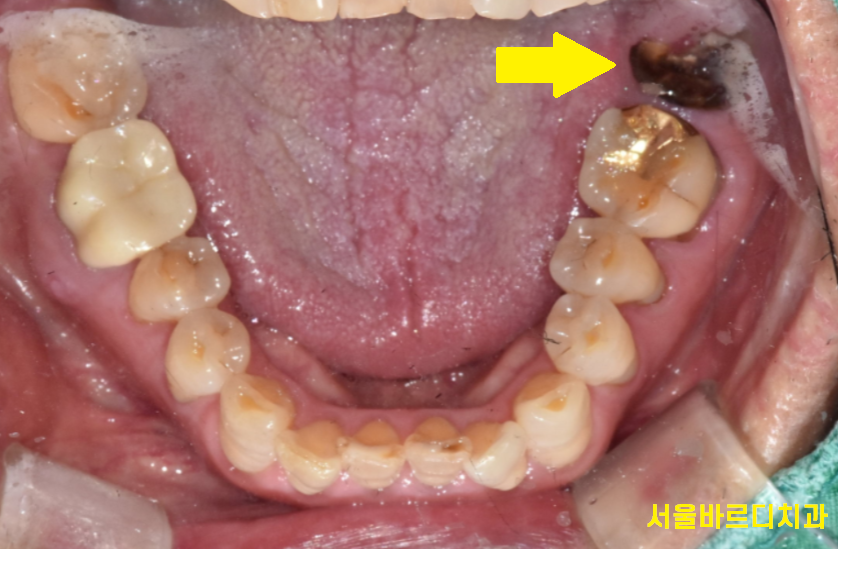

230130

부러진 부위는

까맣게 변했을정도로 상태가 안좋았습니다.